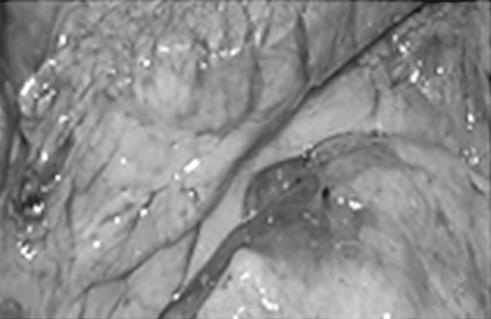

Иллюстрация к книге — Неалкогольная жировая болезнь печени [i_042.jpg]

Отек головного мозга

Рис. 38. Летальный случай пациентки с острым отравлением алкоголем